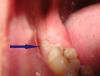

Ester Опубликовано 9 июня, 2013 Автор Поделиться Опубликовано 9 июня, 2013 Верхние точно удалю, там все равно кариес обнаружили, а вот с нижними не могу определиться... в том то и дело, что они не беспокоят. У ортодонта я уже была, даже у двоих: один сказал удалять, второй - не обязательно, можно так оставить. Я боюсь, что я их оставлю, а потом там тоже кариес будет и все равно удалять придется. Так не лучше удалить сейчас, пока я моложе, чем потом, когда они испортятся? И вот фото как это выглядит. Ссылка на комментарий

Ester Опубликовано 1 июля, 2013 Автор Поделиться Опубликовано 1 июля, 2013 Удалила вышеупомянутый зуб 2 недели назад. Был разрез десны и небольшое отпиливание зуба. Потом часть десны зашили, а лунку врач вел под турундами. Отек давно спал, болей никаких нет. Однако в лунке, если немного отодвинуть десну, виднеется кость (что-то белое), край не острый, а где-то в глубине и, в принципе, мне не мешает. Можно оставить все как есть или лучше показаться доктору? Ссылка на комментарий